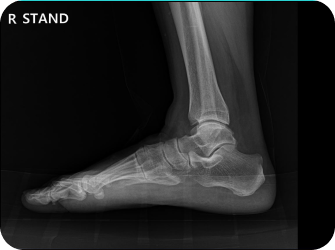

척추 엑스레이 검사

족부 엑스레이 검사

다리길이 엑스레이 검사

족저경 검사

휜다리 증상 확인